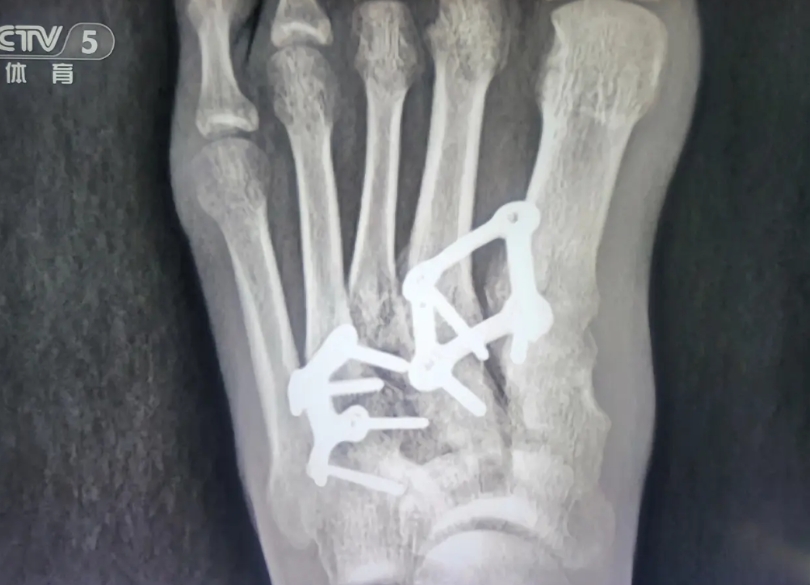

中国式师徒情 世锦赛颁奖仪式后,石雨豪接受央视采访时含泪感激教练:“在我伤痛的8年里,教练一直陪伴着我。我们之间早已不只是教练与队员的关系,更像是一位父亲对待孩子,所以我非常感谢我的教练!” 无独有偶,教练朱华刚在接受采访,谈及石雨豪8年前受伤的情况时,也不禁潸然落泪。二人完美诠释了虽无血缘,却胜似血亲的中国式师徒情。